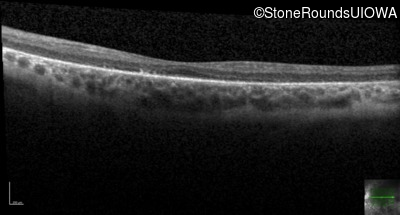

Optical Coherence Tomography - Right - 20/50 +1

Exemplar / OCT Stack

OCT Stack